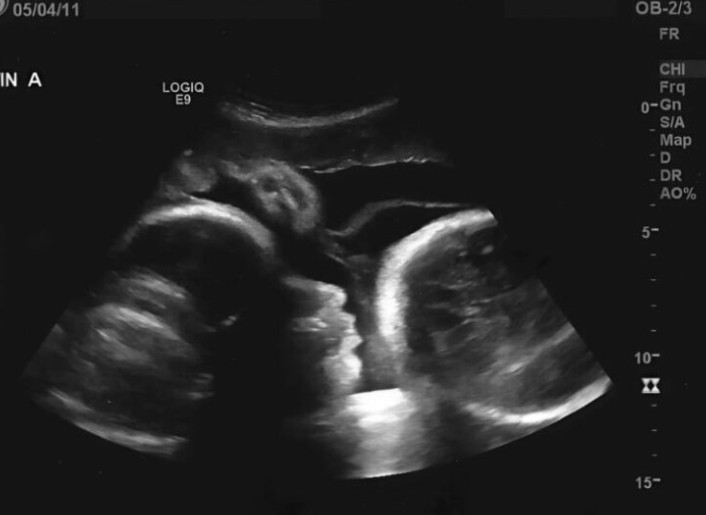

Lékaři při pohledu na obrazovku ultrazvuku okamžitě zbledla tvář a roztřeseným hlasem vyřkl krutou pravdu. Larisa nebyla těhotná; ty úplně první testy poskytly fatálně zavádějící výsledek. Příčinou jejího vyklenutého břicha nebyl rostoucí plod, ale pravý opak – gigantický nádor na vaječníku, který její tělo pomalu sžíral zevnitř.

Slova lékaře byla pro Larisu naprostým zmarem. Onen pocit „pohybů“ v břiše byl ve skutečnosti jen tlakem masy na její vnitřní orgány. Navíc kvůli tomu, že s lékařskou pomocí tak dlouho otálela, se rakovinné buňky nekontrolovaně rozšířily do celého těla. „Kdybyste přišla hned na začátku, dokázali bychom vás zachránit. Teď je však situace kritická,“ udeřil na ni lékař s bolestnou realitou.